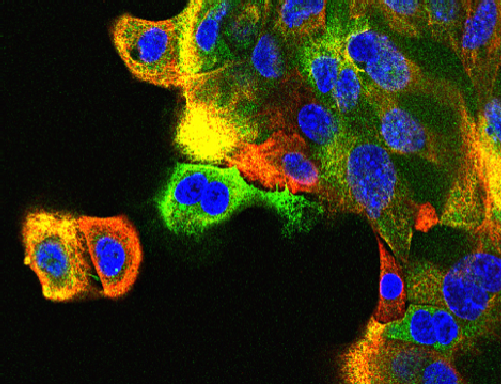

JNK and breast cancer

JNK supression mammary tumor formation. Breast tumor cells isolated from mice with compound JNK-deficiency in the mammary epithelium were stained with antibodies to cytokeratin 5 (red) and cytokeratin 8 (green). DNA was stained with DAPI.